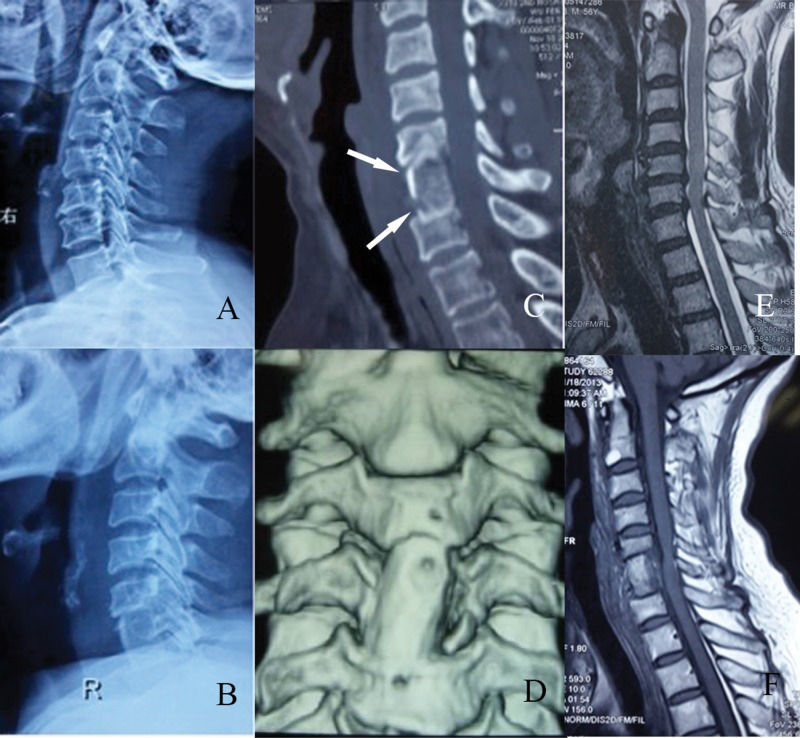

Imaging examinations of a patient who underwent C5-7 fusion. A: Radiograph, lateral view; pre-operation. B: Radiograph, lateral view; post-operation. C: Computed tomography scan, axial view; note the poly L/lactide screws (arrow). D: Three-dimensional reconstruction of the graft. E: Magnetic resonance imaging scan, axial view; pre-operation. F: Magnetic resonance imaging scan, axial view; post-operation.

RESULTSAll of the screws were inserted successfully and no screws were broken. The operation time ranged from 0.6 to 2.2 hours (average 1.2±0.37 hours). Average blood loss during the operation was 133±64 ml (range 50-350 ml). No complications occurred during surgery, such as hematoma, choking, esophageal injury, nerve injury, dural tearing, or cerebrospinal fluid leakage. All of the patients were followed-up for at least 24 months and no patient was lost. In the follow-up, no patients presented foreign body sensations, systemic adverse reactions, or graft prolapse or collapse. No complications such as screw breakage or esophageal injury were encountered. When the symptoms were evaluated by the Japanese Orthopaedic Association (JOA) score, the recovery rate (RR) of 39 patients was above 75%, the RR of 10 patients was 50%-74% and the RR of 7 patients was 25%-49%. RRs higher than 75% are excellent; RRs between 50% and 74% were considered good; and RRs between 25% and 49% were considered fair. The rate of excellent and good improvement was 87.5%. The average duration of graft fusion was 3.8±0.55 months (range 3-5 months, Table 2). X-rays and CT scans showed that the cervical curvature was normal and the height of the vertebrae exhibited no obvious loss (Figure 2B/C). Three-dimensional reconstructions of CT scans demonstrated that the graft fused well with adjacent vertebrae and that the screws were absorbed as predicted (Figure 2D). The MRI findings showed that the cerebrospinal fluid was unobstructed (Figure 2F). No obvious complications appeared throughout the follow-up evaluations.